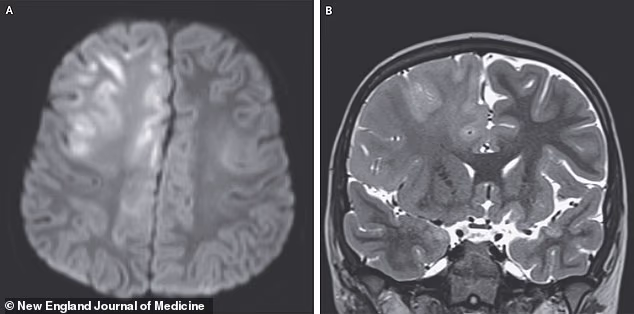

An MRI scan of the child’s brain showed swelling and slowed movement of water molecules in the frontal lobe and corpus callosum, a sign of cell injury or death. The doctors diagnosed the boy with subacute sclerosing panencephalitis (SSPE) caused by his measles infection.

The above images show the child’s brain nearly seven years after he was infected with measles. He died a year later of subacute sclerosing panencephalitis (SSPE)

SSPE progresses over months or years after measles and has a mortality rate of 95 percent. The boy in the case study died a year after his symptoms began, doctors wrote in the New England Journal of Medicine